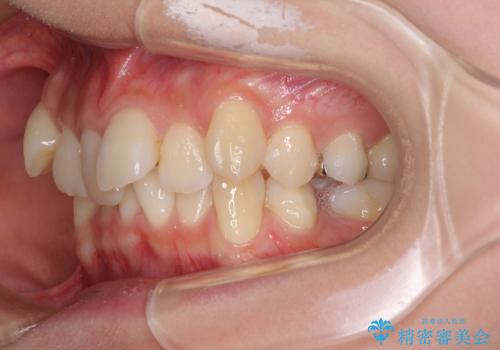

- 前歯の叢生と八重歯を気にして来院された患者様です。

叢生が強く、奥歯の咬合も左右差が大きかったため、上下左右4本を抜歯して、ワイヤー矯正を行うこととしました。

20歳前後と年齢が若かったため、非常にスムーズに歯列が整い、1年半をかけずに治療を終えることができました。